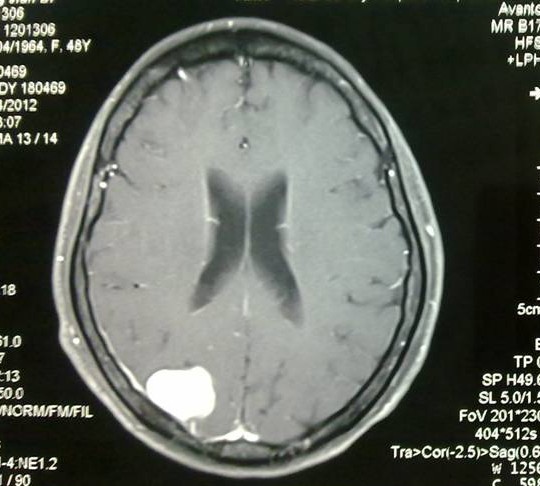

患者女性,49歲,因反復(fù)頭暈、頭痛4年主訴入院。頭顱MRI確診:腦膜瘤。余永強(qiáng)主任主持術(shù)前討論,表示我院目前已經(jīng)具備獨(dú)立開展這類手術(shù)的能力,確定主刀余永強(qiáng)主任、助手梁全醫(yī)師。上午9點(diǎn)30分,手術(shù)正式開始。一切順利進(jìn)行,骨瓣開顱,切開硬膜后,腫瘤呈現(xiàn)在醫(yī)生的眼前。根據(jù)術(shù)前CT定位的骨窗范圍非常準(zhǔn)確,恰好將整個腫瘤完全顯露在中間。移入顯微鏡,利用精致的顯微手術(shù)器械,精準(zhǔn)地沿腫瘤邊緣進(jìn)行分離,整個過程如行云流水般一氣呵成,短短半個小時,已經(jīng)將可見腫瘤絕大部分切除。之后,在作進(jìn)一步的探查中,意外地發(fā)現(xiàn)在靠近矢狀竇的位置,竟然還有一部分腫瘤組織延伸進(jìn)入,緊貼矢狀竇,而這在術(shù)前磁共振上是沒有顯示的。肉眼觀察近似于脂肪組織,其中還有一些血管穿行。單純一塊腫瘤組織好處理,但靠近矢狀竇的話就很麻煩了,稍有不慎,就可能損傷矢狀竇導(dǎo)致術(shù)中大出血。矢狀竇的風(fēng)險(xiǎn),有時候甚至是致命的。

術(shù)前MRI增強(qiáng)成像,腫瘤位于右頂葉,與矢狀竇較為接近,而術(shù)中實(shí)際情況是有一部分腫瘤組織直接貼在矢狀竇壁上,手術(shù)難度比術(shù)前預(yù)計(jì)的更大。